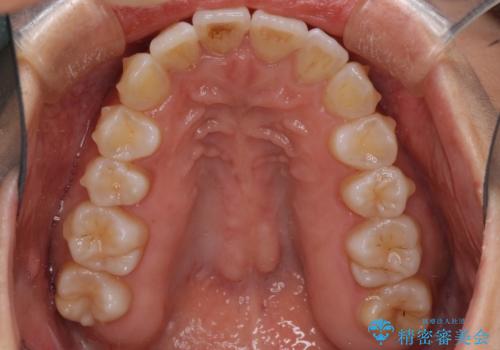

- 上下の歯の前後関係が乱れ、歯に負担がかかるとのことで来院された患者様です。

下顎が右左側に変位しているため、左側奥歯の咬み合わせが上下反対の関係となっていました。

また、上下ともに歯列が狭窄しており、奥歯以外にも反対咬合が認められました。

歯列全体の拡大と、歯と歯の間を削ることでスペースを獲得し、インビザラインによる矯正治療を行うこととしました。

骨格的な問題を抱えた左奥以外は比較的早く咬み合わせが改善しましたが、左奥はどこで咬み合えば良いのか分からず、大変不便な思いをされていました。

ゴムかけにご協力いただき、最終的には反対咬合を改善することができ、患者様には大変満足していただきました。